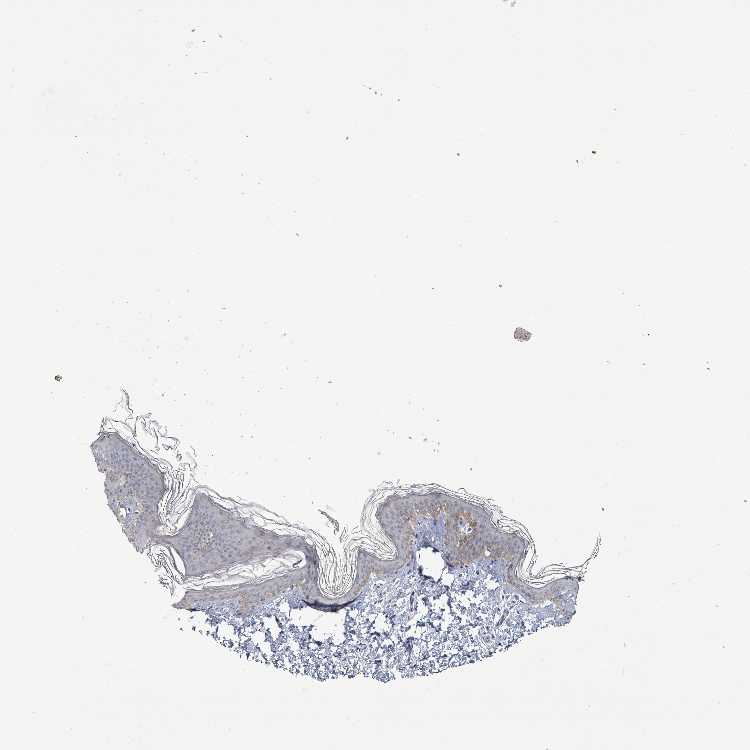

SKIN 1 - Antibody stainingi

Antibody staining in the annotated cell types in the current human tissue is reported as not detected, low, medium, or high, based on conventional immunohistochemistry profiling in selected tissues. This score is based on the combination of the staining intensity and fraction of stained cells.

Each image is clickable and will lead to virtual microscopy that enables deeper exploration of all samples and also displays staining intensity scores, fraction scores and subcellular localization as well as patient and tissue information for each sample.

Antibody HPA043337Antibody HPA048310Antibody HPA069148

Langerhans LowLowNot detected

Fibroblasts LowNot detectedNot detected

Keratinocytes LowLowNot detected

Melanocytes LowLowNot detected